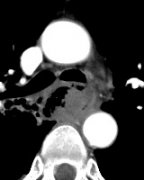

来自于食道癌的出血常常为致命性出血。由于出血病因的缘故,很多医生治疗并不积极。但是出血并不总是来自胸主动脉,也可以来自支气管动脉或肋间动脉的分支,胃左动脉和颈动脉。此时的栓塞往往是有效的,临床成功率将近90%。 病例1 放化疗后 住院期间出血 CT显...